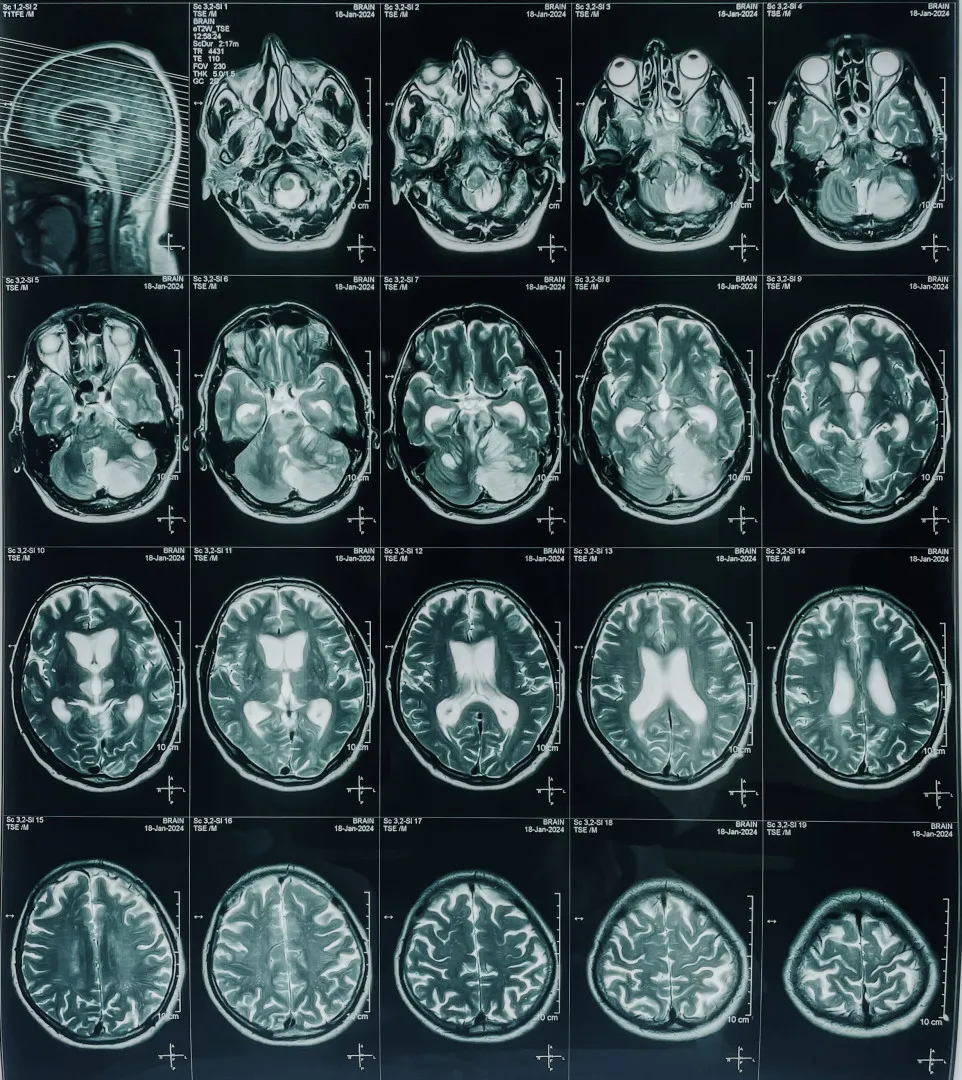

Una vez en el centro médico, los doctores realizarán una tomografía computarizada (TC) o una resonancia magnética para confirmar si se trata de un EVC isquémico. El tratamiento puede incluir la administración de medicamentos trombolíticos para disolver el coágulo o procedimientos quirúrgicos como la trombectomía mecánica, donde se extrae físicamente la obstrucción de la arteria.